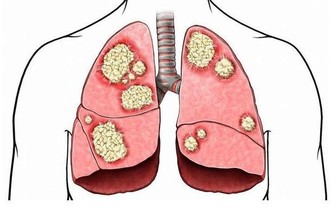

據統計,全世界每年約有120萬婦女發生乳腺癌,有50萬婦女死於乳腺癌,社會對於乳房的關注強度也越來越大,只能說明乳房疾病發生的概率在提高,古方中也列舉了很多類似於乳腺增生、乳腺癌的疾病,如《婦人大全良方》曾提到:“若病初起,內結小核,或如鱉棋子,不赤不痛,積之歲月漸大,岩崩破如熟榴,或內潰深洞……”它同時認為“此屬肝脾鬱怒,氣血虧損,名曰乳岩”,明確地道明了乳腺疾病的誘因也是氣血問題。

情緒暴躁導致乳腺疾病的發生;乳房的內測與腎經有關,乳頭及乳暈與胃經和肝經有關,乳房外側與肝經、膽經、心包經有關。這幾條經絡任何一條出現阻塞都有可能引髮乳房疼痛,如果這種淤堵不能疏通開來,甚至逐年增加,就有可能發生危及生命的乳腺癌,所以及時疏通與乳房想通的經絡是預防和治療乳腺疾病的關鍵,而各條經絡的氣血充足,則是乳房保養的根本。